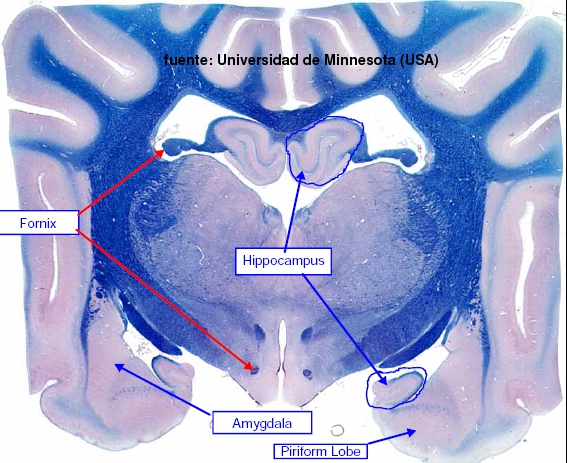

El Sistema Olfatorio y el Sistema Límbico.

El Sistema Olfatorio es el encargado de recoger las sensaciones del olfato. Las neuronas de primer orden o células receptoras son neuronas bipolares localizadas en el EPITELIO OLFATORIO. Los axones no mielinizados de estas neuronas se recogen en manojos que colectivamente forman el NERVIO OLFATORIO. Este nervio penetra la LÁMINA CRIBIFORME del hueso etmoides para entrar en el BULBO OLFATORIO, donde se encuentran las células mitrales (neuronas de segundo orden) las cuales envían sus axones formando el TRACTO OLFATORIO o ESTRIA. El bulbo olfatorio consta de varias capas: una glomerulas (donde las fibras de los nervios olfatorios sinapsan con las dendritas de las células mitrales), una capa de células mitrales y una capa de células granulares.

El tracto olfatorio termina por una bifurcación en la ESTRIA OLFATORIA MEDIAL y LATERAL, las cuales proyectan respectivamente al AREA SEPTAL (responsable de los reflejos olfatoviscerales) y a la CORTEZA PIRIFORME (responsable de la sensación consciente de la olfación).

El RINENCÉFALO está formado por el lóbulo piriforme y por el bulbo olfatorio.

El Sistema Límbico comprende a estructuras de la corteza cerebral que bordean el tronco encefálico, junto a ciertos componentes del hipotálamo, tálamo y epitálamo, y está relacionado con la percepción de las emociones de importancia para la supervivencia del animal, como la defensa, alimentación, escape, etc.. y emociones asociadas con la supervivencia de la especie, tales como la defensa territorial, cortejo, apareamiento, etc.., estando además relacionado con procesos relativos al aprendizaje y memoria.

HIPOCAMPO: Es una estructura de la corteza cerebral con 3 capas de células, llamada ARQUEOCORTEX, de importancia en aprendizaje asociativo y memoria (particularmente memoria de corto tiempo). Tanto pacientes amnésicos como animales con daños en hipocampo exhiben problemas tiempo-dependientes en tareas de comportamiento generalmente descritas como asociativas o relacionadas por naturaleza. Este área del cerebro tiene un bajo umbral de ataques o convulsiones.

AMIGDALA: Es una región altamente diferenciada cerca del polo temporal de los hemisferios cerebrales de los mamíferos. Es un núcleo basal que está implicado en la emoción, memoria, comportamiento social, comportamiento reproductor, miedo y agresión, y modulación de sistemas autonómicos y neuroendocrinos. Muchos de sus efectos son opuestos a los del septum. Lesiones de la amígdala pueden suponer comportamiento dócil, mientras que su estimulación produce comportamiento agresivo.

AREA SEPTAL o SEPTUM: este área de la corteza cerebral está envuelta en varios procesos fisiológicos y de comportamiento, tales como emociones, alivio del miedo, comportamiento dócil y estrés, además de en procesos de regulación autonómica ( ingesta de comida o agua, hibernación, etc..). Su estimulación lleva a un comportamiento dócil, y puede suprimir muchas respuestas autonómicas.

LÓBULO PIRIFORME del RINENCÉFALO. Entra dentro del sistema límbico ya que tiene funciones afectivas junto a otras estructuras límbicas tales como impulsos o ciertas conductas de comportamiento.